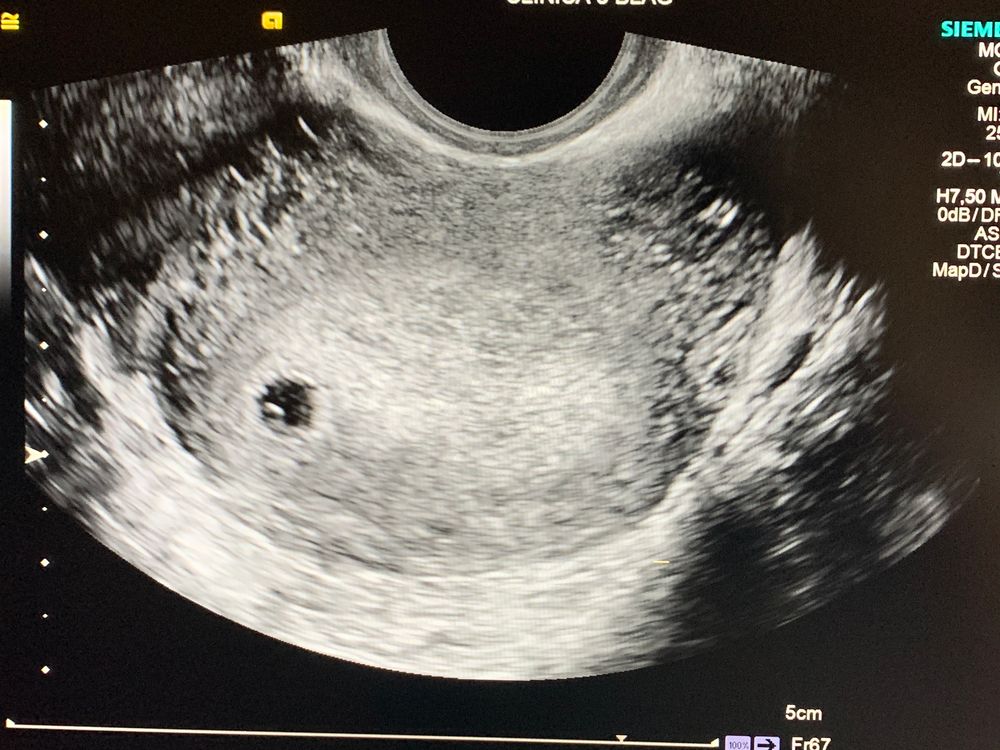

УЗИ 5 недель 1 день